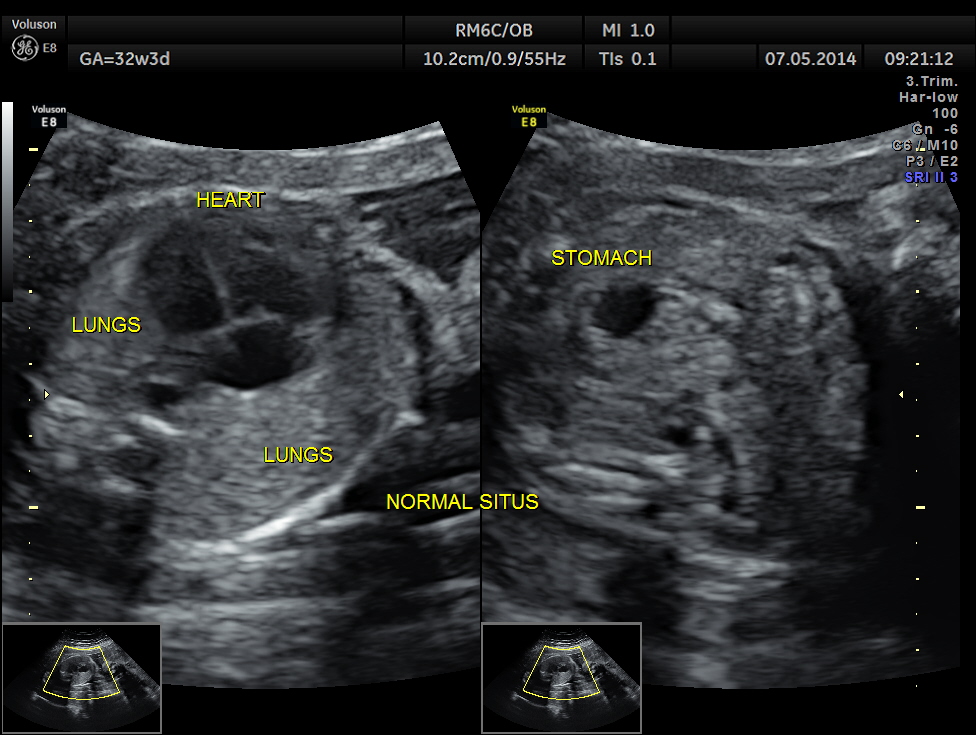

This was a 37 year old lady , a primi gravida referred for evaluation of intra uterine growth restriction. As per LMP the GA was 32 w 3 Days, but as per AUA the GA was 26 weeks . All the long bones were < 5.0 % tile. But cerebellum was 42.7 % tile. There was severe symmetrical growth restriction .

The echo pictures are given below.

Cardiac axis is abnormal.

LA & LV appear to be smaller than RA & RV.

The situs appeared to be normal.